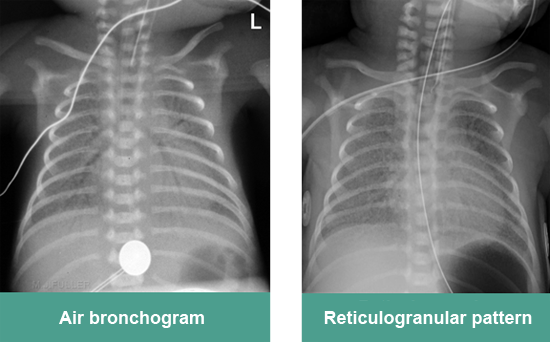

7. Typical X-ray finding of RDS/ HMD

► Decreased lung volume

► Reticulogranular pattern

► Ground glass opacification

► Air bronchograms

► White out lungs